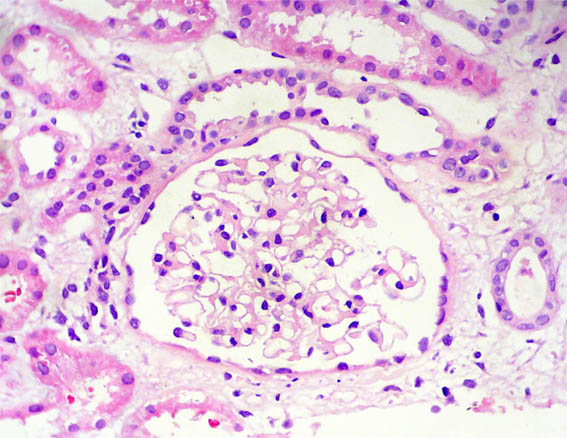

Figura 5.

H&E, X400.